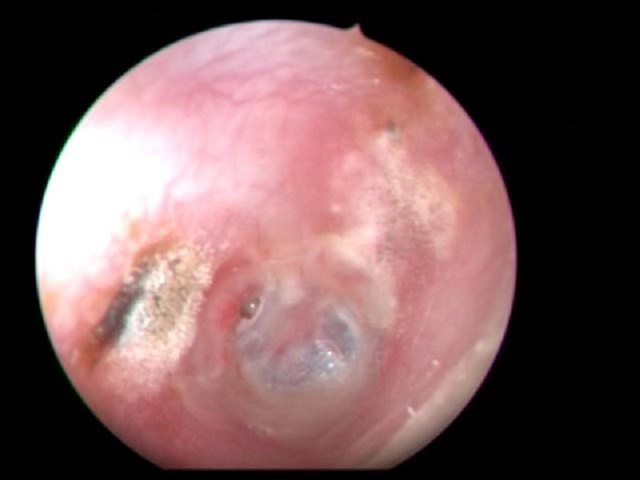

Hình ảnh nội soi trước phẫu thuật ghi nhận bệnh nhân bị viêm tai giữa mạn tính, thủng màng nhĩ tai phải

Tại đây, các bác sĩ tiếp tục chẩn đoán bệnh nhân bị viêm tai giữa mạn tính thủng nhĩ tai phải. Sau 1 tuần sử dụng kháng sinh tai bệnh nhân hết chảy dịch nhưng tình trạng đau đầu vấn dữ dội, kèm theo mờ mắt phải, hàm răng trên đau buốt. Các bác sĩ quyết định kiểm tra hình ảnh, truy tìm nguyên nhân của tình bệnh nhưng trên phim CT-Scan không phát hiện bất thường. Căn cứ trên bệnh sử về can thiệp vá màng nhĩ người bệnh đã được thực hiện, bác sĩ quyết định phẫu thuật mở thượng nhĩ để kiểm tra.